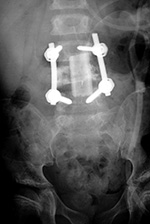

| Steffee pedicle plates and screws |

| Frontal and lateral views in two different patients show bilateral Steffee plates and screws in the lumbar spine with two side by side Brantigan intervertebral cages (arrows) at L2-3. |